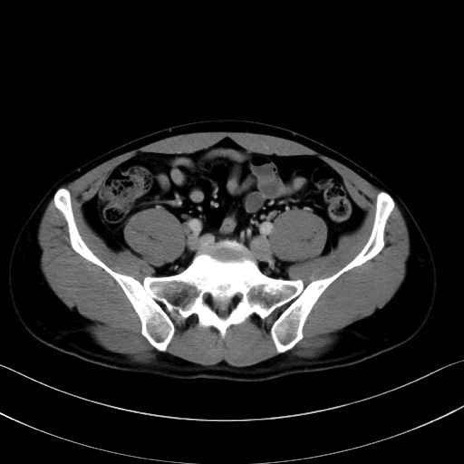

小殿筋 (Gluteus minimus)